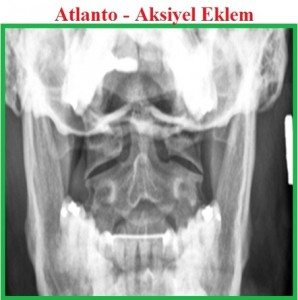

Servikal eklemler: 1.Atlanto-oksipital. 2.Atlanto-aksiyel; atlanto-odontoid, lateral atlanto-aksiyel. 3.Unkovertebral (luschka eklemi). 4.İntervertebral eklemler.——-Korpus-korpus eklem; fibrokartilojenoz intervertebral disk (anulus fibrozus, nukleus pulpozus).